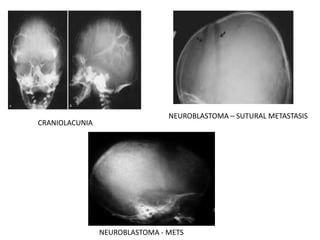

Children

• Craniolacunia

• Wormian Bones

• Increased Convolutional Markings

• Histiocytosis

• Metastasis – neuroblastoma, leukemia, Ewing’s Sarcoma

CRANIOLACUNIA

NEUROBLASTOMA – SUTURAL METASTASIS

NEUROBLASTOMA - METS